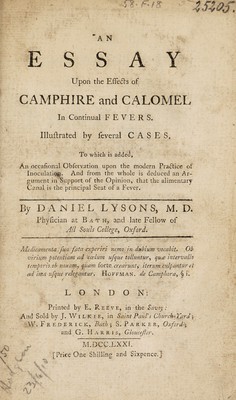

An essay upon the effects of camphire and calomel in continual fevers ... To which is added, an occasional observation upon the modern practice of inoculation. And from the whole is deduced an argument ... that the alimentary canal is the principal seat of a fever / [Daniel Lysons].

- Lysons, Daniel, 1727-1800

- 1771

Credit: An essay upon the effects of camphire and calomel in continual fevers ... To which is added, an occasional observation upon the modern practice of inoculation. And from the whole is deduced an argument ... that the alimentary canal is the principal seat of a fever / [Daniel Lysons]. Source: Wellcome Collection.